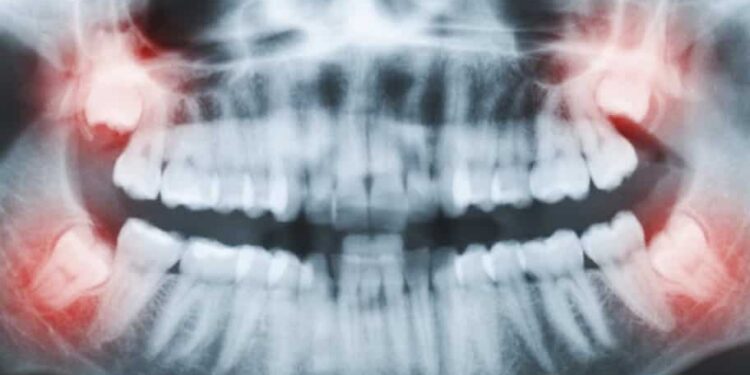

The Best Wisdom Teeth Removal Melbourne Treatment is a surgical procedure that will take one or more wisdom teeth. As you know, Humans have four permanent adult teeth located at the back corners of their body. Whenever there is not enough space for wisdom teeth growth, it can become impacted. These impacted wisdom teeth can create pain and other dental problems. Oral Surgeons will recommend undergoing surgery to avoid dental problems in later life. Here is an overview of the best wisdom teeth removal treatment.

Whenever you fail to undergo the best wisdom teeth removal Melbourne Treatment, you will likely face some serious oral health problems. If the wisdom teeth are left untreated, you may experience severe pain and trapping and debris of the food behind the wisdom teeth. The impacted wisdom teeth will also cause infection and gum disease which are commonly called periodontal disease. In addition to the wisdom teeth, the impacted teeth will damage the nearby tooth or surrounding bone. The untreated Wisdom teeth are going to develop a fluid-filled sac around the wisdom tooth, which further leads to complicate the braces to straighten other teeth.